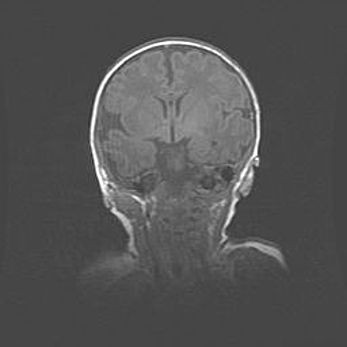

Множественные кисты обоих полушарий головного мозга, наибольшая из них в правой затылочной области. Ассиметричная атрофическая гидроцефалия.

Возраст: 7 месяцев

Вес: 5660 г

Пол: мужской

Окружность головы: 41,5 см

Срок гестации: 28-29 недель

Кисты головного мозга развиваются в результате многоочаговых некрозов вещества мозга и возникают вследствие перенесенной перинатальной инфекции, менингитов, энцефалитов, асфиксии, родовой травмы, расстройств мозгового кровообращения различного генеза. Образованию кист в веществе головного мозга плодов и новорожденных способствуют такие факторы, как высокое содержание в нем воды, недостаточная (или отсутствие) миелинизация и слабая астроглиальная реакция на повреждение.

Кисты могут сочетаться с гидроцефалией и другими поражениями головного мозга.